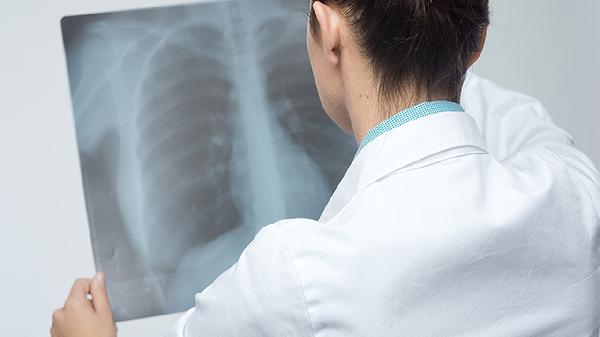

肺气肿合并肺部结节的情况大多数不会发展成癌症,但具体是否会有癌变风险,还需要根据结节的特性来综合判断。影响因素主要包括结...